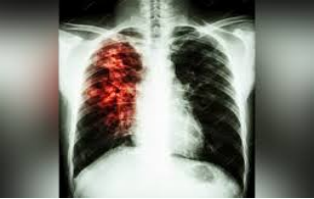

Туберкульоз — інфекційне захворювання, спричинене мікобактеріями туберкульозу (бактеріями комплексу Mycobacterium tuberculosis).